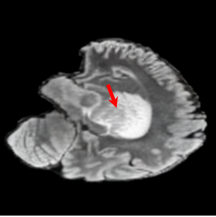

To see when and how X-Diffusion fails, we conducted an experiment on healthy brains (no tumour) using IXI dataset, by running an X-diffusion trained on BRATS brain tumor dataset. Our X-Diffusion achieved a PSNR of 35.86 dB on the IXI dataset despite being trained on the BRATS dataset. We then ran the tumour segmenter on the set of 582 healthy scans and corresponding generated MRIs. The segmenter predicted tumours in 9.9% of the real healthy brains and in 11.3% of the generated brain MRIs. Some of these tumor hallucination examples fron X-Diffusion generation are shown in Figure 10.

| Hallucination | Reference | Hallucination | Reference | Failure | Reference |

This shows how the generated MRIs indeed preserve the tumour information and can act as an affordable and informative pseudo-MRI, before conducting an actual costly MRI examination in hospitals. Given that our model has been trained on brain scans all with tumours, we expect to see hallucinations of tumours in healthy scans. We report two cases of failure of our model in Figure VII. Hallucinations of tumours on healthy samples represent 2% of the test set.